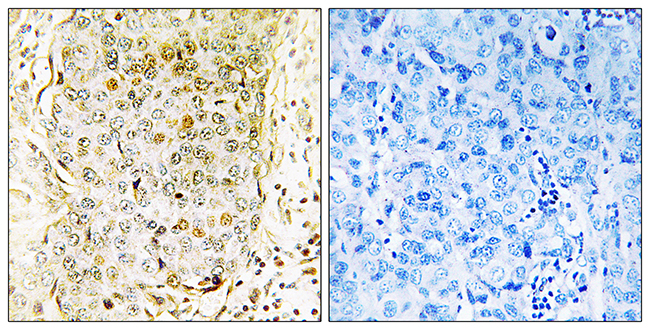

Anti-MLK3 AntibodyA97779

ApplicationsELISA, ImmunoHistoChemistry

ReactivityHuman, Mouse, Rat